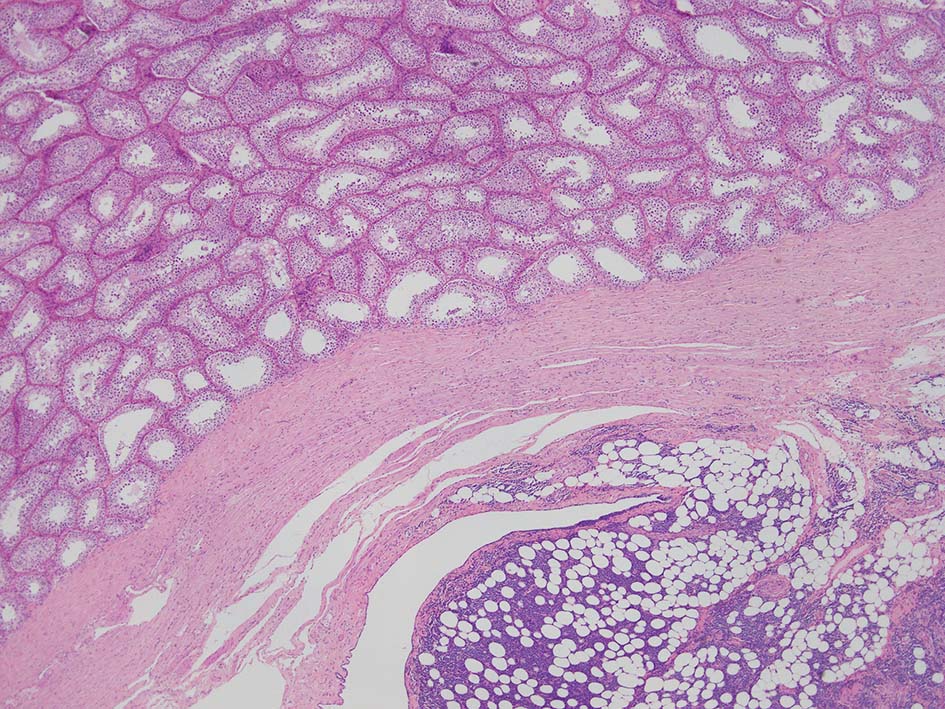

精巣上体, 精巣周囲脂肪織への浸潤, 精巣実質, 白膜の非浸潤部

loupe像Aの領域: 精細管をスペアするように, 小型リンパ球優位, 一部中型のlymphoid cellsがシート状密に浸潤増殖する. tubulesのほとんどにはlymphoid cellsが浸潤していないが, LELに似たようなlympho-tubular lesionが少数認められた. x400高倍率では, 増殖細胞は, 粗く, 凝集したクロマチンをもつ類円形, non-cleavedな核をもつ細胞質の乏しいlymphoid cellsである. 核小体か凝集したクロマチンかわかりにくい.

loupe像では, 腫瘍細胞が髄様密に浸潤増殖する部位と, 精細管をスペアするように管間に腫瘍細胞が浸潤する部分(右端図 A)がある.